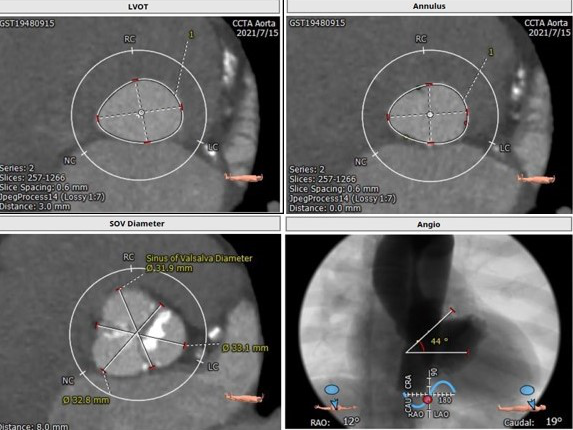

主动脉CTA:三叶瓣,瓣环面积为518 mm²,严重钙化;法式窦结构可,主动脉瓣瓣环周径82.3 mm,平均直径26.2mm,左室流出道周径28.0mm,主动脉窦管交界处(STJ)高28.9 mm;左冠高度14.8mm,右冠高度17.2mm,升主动脉未见明显增宽,主动脉根部角度44°,左室大(66.9mm),心尖部局部心肌薄弱,推荐右侧股动脉做为主入路。推荐使用26号瓣膜。